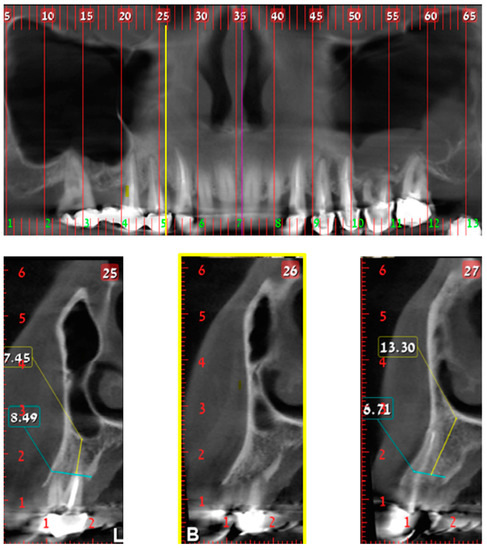

An Efficient Hybrid 3D Computer-Aided Cephalometric Analysis for Lateral Cephalometric and Cone-Beam Computed Tomography (CBCT) Systems

by Laurine A. Ashame, Sherin M. Youssef, Mazen Nabil Elagamy and Sahar M. El-Sheikh

Lateral cephalometric analysis is commonly used in orthodontics for skeletal classification to ensure an accurate and reliable diagnosis for treatment planning. However, most current research depends on analyzing different type of radiographs, which requires more computational time than 3D analysis. Consequently, this study [...] Read more.

Lateral cephalometric analysis is commonly used in orthodontics for skeletal classification to ensure an accurate and reliable diagnosis for treatment planning. However, most current research depends on analyzing different type of radiographs, which requires more computational time than 3D analysis. Consequently, this study addresses fully automatic orthodontics tracing based on the usage of artificial intelligence (AI) applied to 2D and 3D images, by designing a cephalometric system that analyzes the significant landmarks and regions of interest (ROI) needed in orthodontics tracing, especially for the mandible and maxilla teeth. In this research, a computerized system is developed to automate the tasks of orthodontics evaluation during 2D and Cone-Beam Computed Tomography (CBCT or 3D) systems measurements. This work was tested on a dataset that contains images of males and females obtained from dental hospitals with patient-informed consent. The dataset consists of 2D lateral cephalometric, panorama and CBCT radiographs. Many scenarios were applied to test the proposed system in landmark prediction and detection. Moreover, this study integrates the Grad-CAM (Gradient-Weighted Class Activation Mapping) technique to generate heat maps, providing transparent visualization of the regions the model focuses on during its decision-making process. By enhancing the interpretability of deep learning predictions, Grad-CAM strengthens clinical confidence in the system’s outputs, ensuring that ROI detection aligns with orthodontic diagnostic standards. This explainability is crucial in medical AI applications, where understanding model behavior is as important as achieving high accuracy. The experimental results achieved an accuracy exceeding 98.9%. This research evaluates and differentiates between the two-dimensional and the three-dimensional tracing analyses applied to measurements based on the practices of the European Board of Orthodontics. The results demonstrate the proposed methodology’s robustness when applied to cephalometric images. Furthermore, the evaluation of 3D analysis usage provides a clear understanding of the significance of integrated deep-learning techniques in orthodontics. Full article